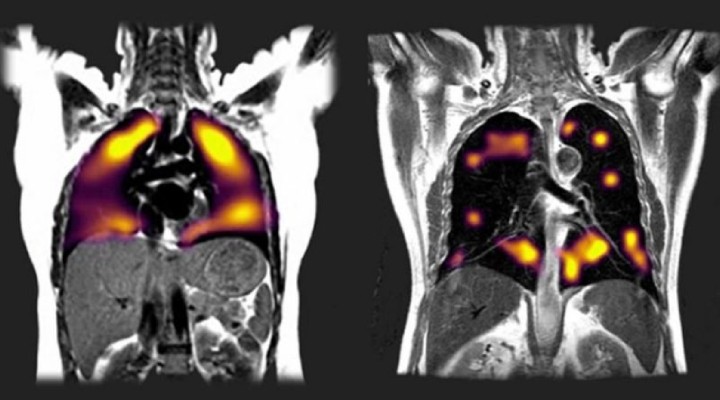

Oxford Üniversitesi’nde 10 hasta üzerinde yapılan araştırmada, yeni bir tarama tekniği kullanılarak, normal taramalarda tespit edilemeyen akciğer hasarlarına rastlandı. Bu yeni tarz EMAR’da (manyetik rezönans görüntüleme) ksenon (zenon) gazı kullanılarak akciğerdeki hasarın kapsamı tespit ediliyor.

Bunların sekizi, yoğun bakıma kaldırılmamış ve solunum cihazına bağlanmamış olmalarına rağmen, koronavirüse yakalanmalarının üzerinden üç ay geçtikten sonra bile nefes darlığı ve yorgunluktan şikayet ediyordu. Normal taramalarda akciğerlerinde herhangi bir soruna rastlanmamıştı.

Ksenon gazıyla yapılan taramalarda ise bu hastalarda akciğer hasarı belirtilerine rastlandı. Kana rahat oksijen akışı olmayan bölgeler tespit edildi. Gleeson, taramalar sonucunda hastalarda ortaya çıkan hasar boyutunun beklediklerinden fazla olduğunu kaydetti.

60 yaş üzeri hastalarda ağır hastalık ve ölüm riski büyük ölçüde artıyor. Fakat denemelerde akciğer hasarının farklı yaş gruplarında ve hastanede tedaviye ihtiyaç duymayanlarda bile tespit edilmesi halinde “hedeflerin gözden geçirilmesi gerekecek”. Gleeson, ksenon gazıyla saptanan akciğer hasarının, koronavirüsün uzun vadeli etkisini ifade eden ve uzatmalı Covid olarak adlandırılan sorunun kaynağı olabileceğini söylüyor.

Tarama tekniği Sheffield Üniversitesi’nden Prof. James Wild’ın başkanlık ettiği bir ekip tarafından geliştirilmişti. Wild, bu tekniği Covid-19’dan kaynaklanan akciğer hasarını ve etkilerini gösterecek “biricik” yöntem olarak niteledi.